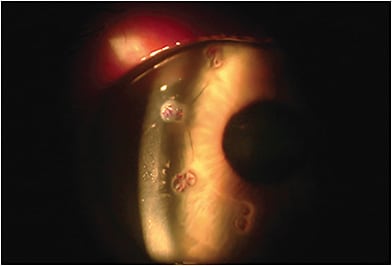

ICRS are polymethyl methacrylate pieces implanted in the mid-peripheral deep stroma to reduce central corneal curvature, and were originally developed as a treatment for myopia. (Figure 2).

When combined with CXL, done to halt the progression of KC, ICRS have been shown effective in improving both BCVA and UCVA in KC by regularizing and decreasing pathologic corneal steepening and irregular astigmatism.7 Studies have shown that insertion of ICRS prior to CXL may have a stabilizing effect on the visual outcomes from the ICRS, and further enhance its effect, whereas prior CXL may have already fixed the cornea into a suboptimal configuration, which ICRS may have difficulty in reversing.8 More studies that have larger cohorts would need to be done to further elucidate these effects.